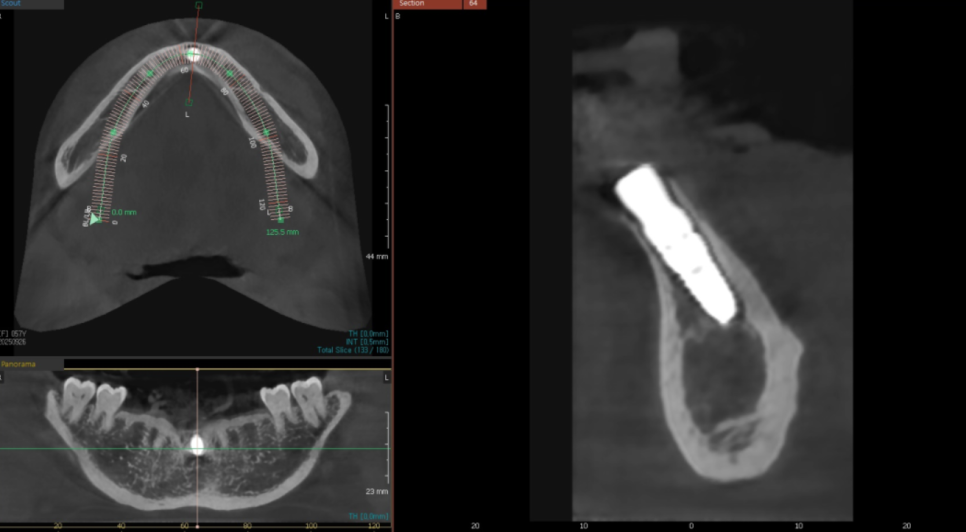

치석으로 인해 뼈가 많이

약해진 상태였기에,

발치 당일 뼈이식과

임플란트 식립을 함께 진행했습니다.